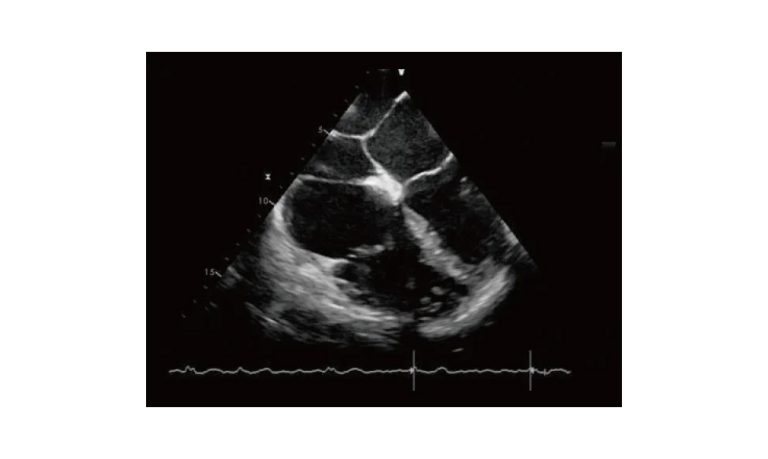

Ultrasound

Wide range of Ultrasound machines that suites a variety of applications from abdominal to rectal scans, we take in consideration how the world is moving towards mobility and mobile applications.

SonoScape Pro Pet E11

Smart Imaging

Introducing the first portable ultrasound with the C-Field+TM platform, redefining diagnostic imaging. Designed for veterinarians, it delivers unmatched clarity, ultra-fast processing, and seamless adaptability for all species. Experience Smart Imaging, Heartfelt Care—anywhere.

Equipped with cutting-edge veterinary software and optimized workflows, it embodies our commitment to Smart Imaging, Heartfelt Care – Wherever Their Journey Leads, with unparalleled performance and adaptability, this innovative system empowers veterinarians to provide exceptional care across all diagnostic applications,

Esaote MyLab Sigma; So Fast, So Easy

Esaote’s new MyLab™SigmaVET is the smart, portable solution that allows use of an ultrasound whenever a quick and complete diagnosis is required.

EBIT50/60 VET

All the power you need

The EBit provides all the power you need for today´s challenging clinical environment, yet remain ultra-portable, ultra-affordable. With its cutting-edge imaging technologies, precise and intuitive workflow, ergonomic and eco-friendly design, versatile transducers for all applications from top to toe, we firmly believe the EBit to be the very best portable ultrasound in its class today.

ECO5 VET

Ultra-Portable, Ultra- Affordable, Color doppler

The multi-purpose user presets, comprehensive measurement & report system, built-in EasyView image achieve system, quick image storage / retrieve / transfer, one-button direct print, make the complete workflow better than what you can dream of.